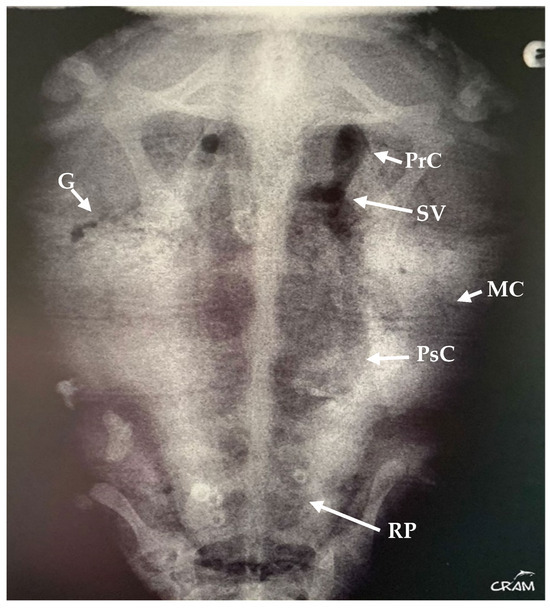

Hard edema with increased periarticular soft tissue and pain was noticed at palpation during clinical evaluation in veterinary medicine [21]. At the beginning of signs, radiographic lesions were polyostotic and poorly defined (Figure 5 and Figure 6).

Early-stage lesions at day 45 of rehabilitation were characterized by a purely osteolytic process restricted to the distal end of the humerus and femur and the proximal end of the radius, ulna, and tibia, including demineralization of the surrounding bones. Osteolytic lesions were restricted to the epiphysis and metaphysis of long bones, and no lesions were detected in the diaphysis.

Figure 5. Dorsoventral radiograph of the right front flipper at day 45 of rehabilitation. Well-defined bone lesions (arrows) are noted. Lesions are lytic with relevant osteopenia and no bone remodeling. The lytic process is seen communicating with the joint space in the elbow joint.